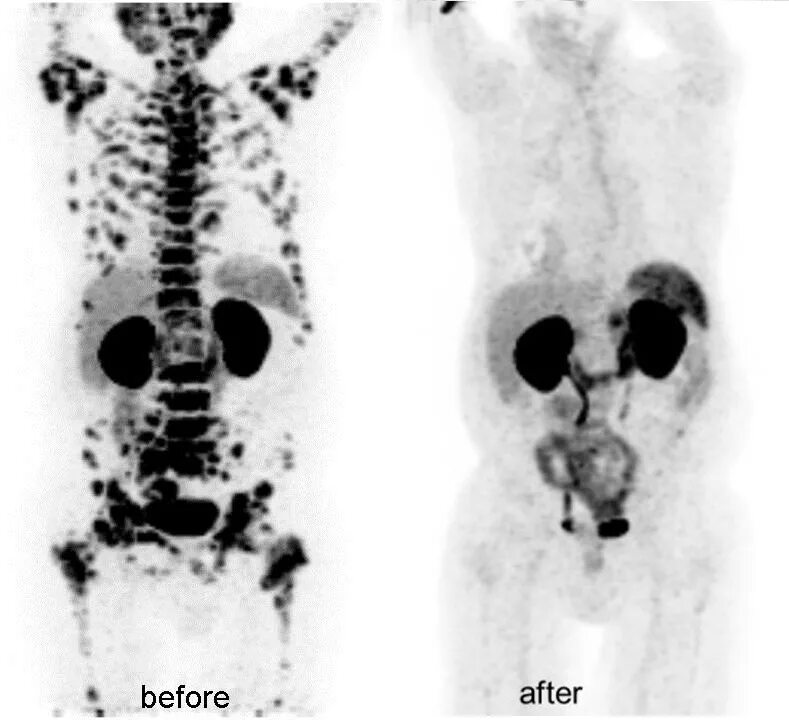

Пэт псма что это